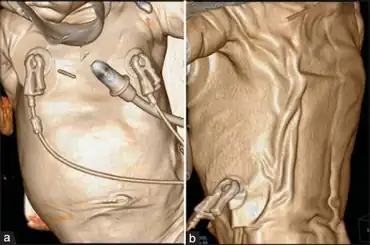

| Diagnostic method | CT scan, MRI [4] |

In terms of the diagnosis of arterial tortuosity syndrome can be done via genetic testing,[8] as well as the following listed below:[4]

- CT

- MRI

- Echocardiogram